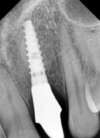

3- Les implants en remplacement d'une dent traumatisée

Cette incisive a subit un choc il y longtemps, progressivement sa racine s'est résorbée et elle s'est infectée.

Après décontamination du site et réalisation d'une technique combinée pose d'implant/greffe de gencive/régénération osseuse guidée a permis de réaliser une empreinte pour confectionner une couronne provisoire immédiate sur implant.

La couronne peut être installée 48 heures après la mise en place de l'implant

Après une période de cicatrisation de 4 mois une couronne définitive en céramique est réalisée